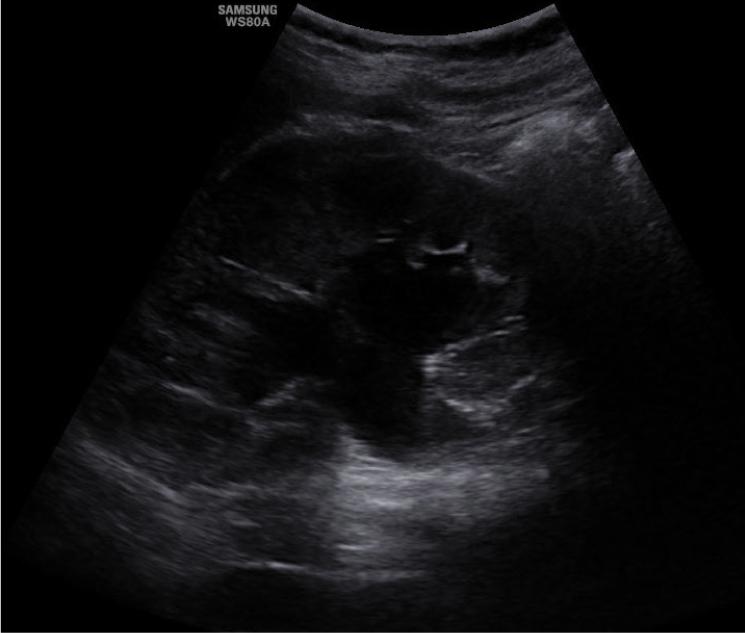

Fig. 2.

Ultrasound assessment of the right kidney (longitudinal section). Visible dilatation of the pelvis and major calyces